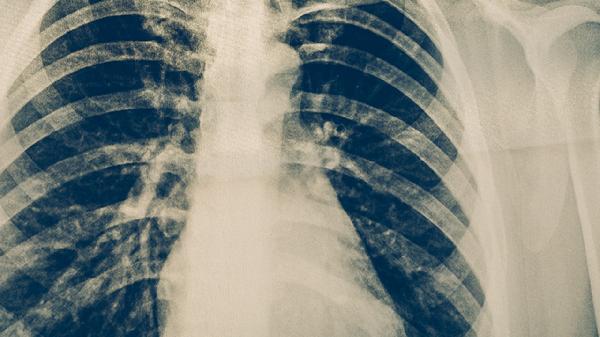

肺结核病的七种可能症状

肺结核病可能出现咳嗽、咳痰、咯血、胸痛、发热、盗汗、体重下降等症状。肺结核病是由结核分枝杆菌感染引起的慢性传染病,主要通过呼吸道传播,建议患者及时就医,在医生指导下进行规范治疗。

肺结核病患者应注意休息,保证充足睡眠,避免过度劳累。饮食上应增加优质蛋白和维生素摄入,如鸡蛋、牛奶、瘦肉、新鲜蔬菜水果等。保持居住环境通风良好,避免到人群密集场所,咳嗽、打喷嚏时注意遮掩口鼻。严格遵医嘱用药,完成全程治疗,定期复查胸部影像学和痰菌检查。密切接触者应进行结核菌素试验筛查。出现症状加重或药物不良反应时应及时就医。